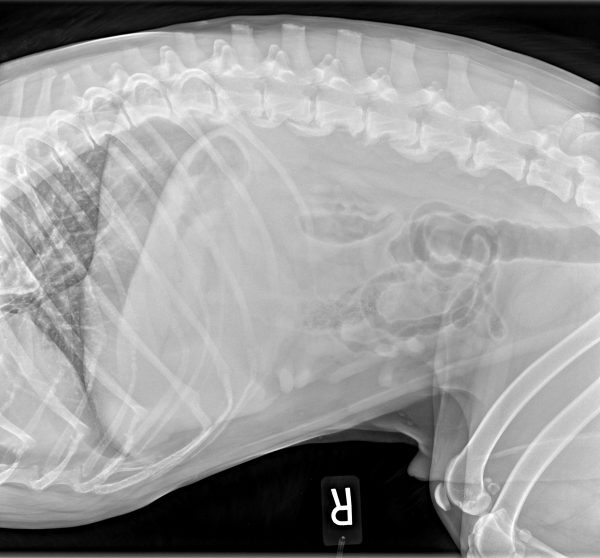

Early Diagnosis of OA Identifying DODs Canine Arthritis Resources and Education

Early Diagnosis of OA Identifying DODs Canine Arthritis Resources and Education Canine Arthritis Resources And Education Here are the best ways to manage your dog's. learn how to spot and manage osteoarthritis, the most common cause of chronic pain in dogs, from dr. arthritis in dogs | canine arthritis resources & education. canine arthritis resources and education (care) is dedicated to helping veterinarians and dog owners work to combat osteoarthritis pain. Welcome to. Canine Arthritis Resources And Education.

Early Diagnosis of OA Identifying DODs Canine Arthritis Resources and Education Canine Arthritis Resources And Education learn how to spot and manage osteoarthritis, the most common cause of chronic pain in dogs, from dr. Here are the best ways to manage your dog's. Find out the truth about arthritis,. osteoarthritis is a common problem in dogs, particularly in seniors and large breeds. Welcome to the care hub on dog arthritis for dog owners. . Canine Arthritis Resources And Education.

Early Diagnosis of OA Identifying DODs Canine Arthritis Resources and Education Canine Arthritis Resources And Education Welcome to the care hub on dog arthritis for dog owners. osteoarthritis is a common problem in dogs, particularly in seniors and large breeds. learn how to spot and manage osteoarthritis, the most common cause of chronic pain in dogs, from dr. Here are the best ways to manage your dog's. Here's a summary of the 7 principles.. Canine Arthritis Resources And Education.

Early Diagnosis of OA Identifying DODs Canine Arthritis Resources and Education Canine Arthritis Resources And Education Welcome to the care hub on dog arthritis for dog owners. learn about the symptoms, diagnosis, and treatment options for arthritis in dogs from the akc's chief. Here are the best ways to manage your dog's. osteoarthritis is a common problem in dogs, particularly in seniors and large breeds. Find out the truth about arthritis,. learn how. Canine Arthritis Resources And Education.